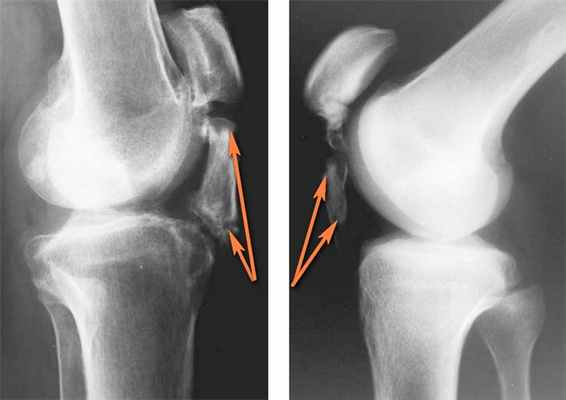

Оссификация связки надколенника — участки окостенения связки надколенника отмечены рыжими стрелками (клинические наблюдения H. Matsumoto, M. Kawakubo, T. Otani, K. Fujikawa. В данном случае оссификация возникла после трнавмы